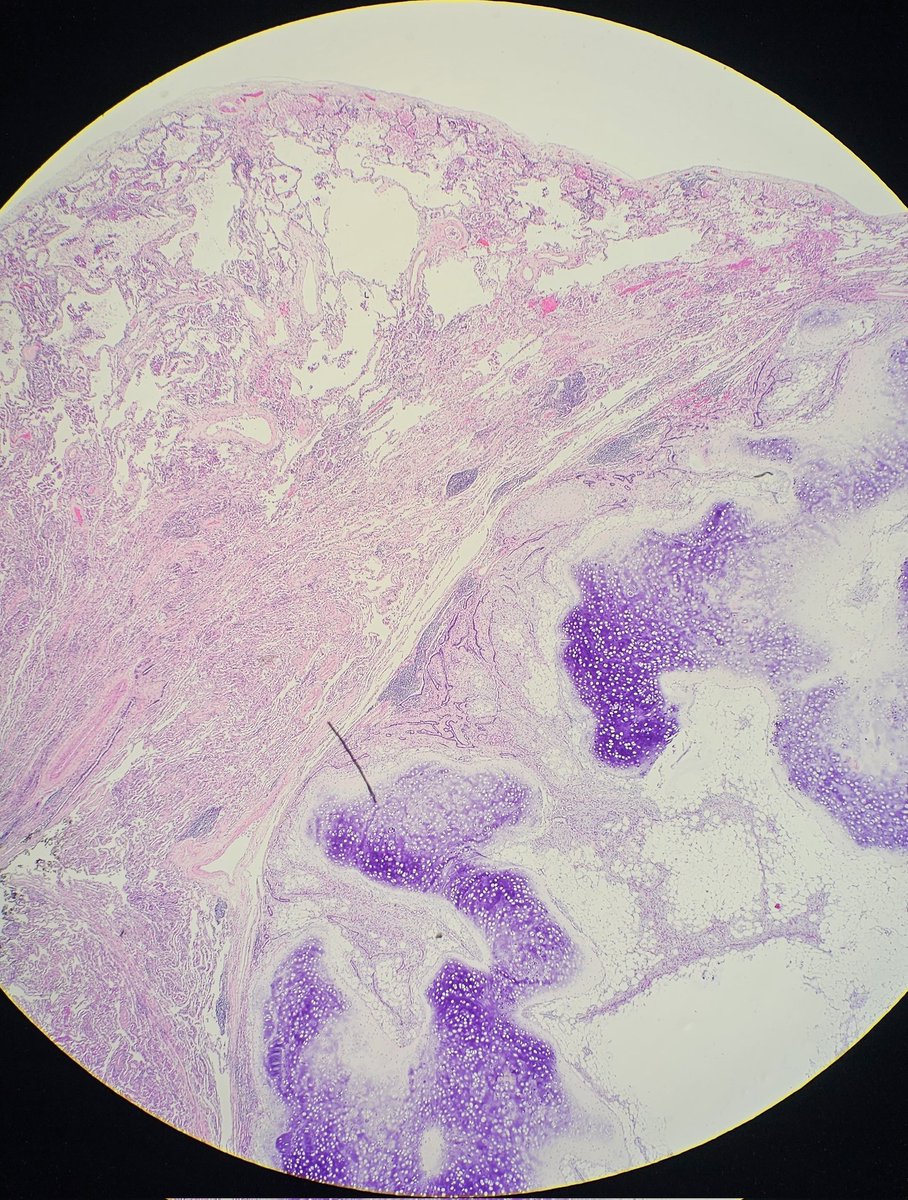

@JenyaMD

Young female with untreated HIV presents with GI bleeding and adenopathy. Which stain or stains would be the most useful to determine the cause of her symptoms? Pictures: Colon Bx, Mesenteric lymph node, Omentum #GIpath #pathology